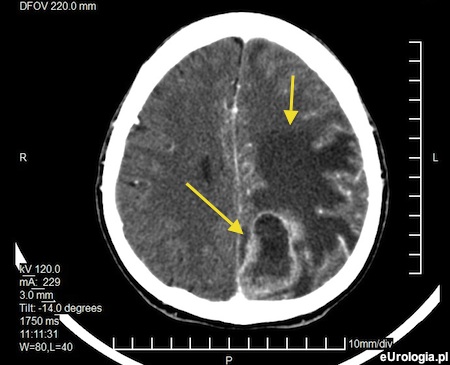

Fot. Skan tomografii komputerowej u wykonanej u pacjenta z przerzutowym rakiem gruczołu krokowego. Strzałkami zaznaczono ogniska metastatyczne.